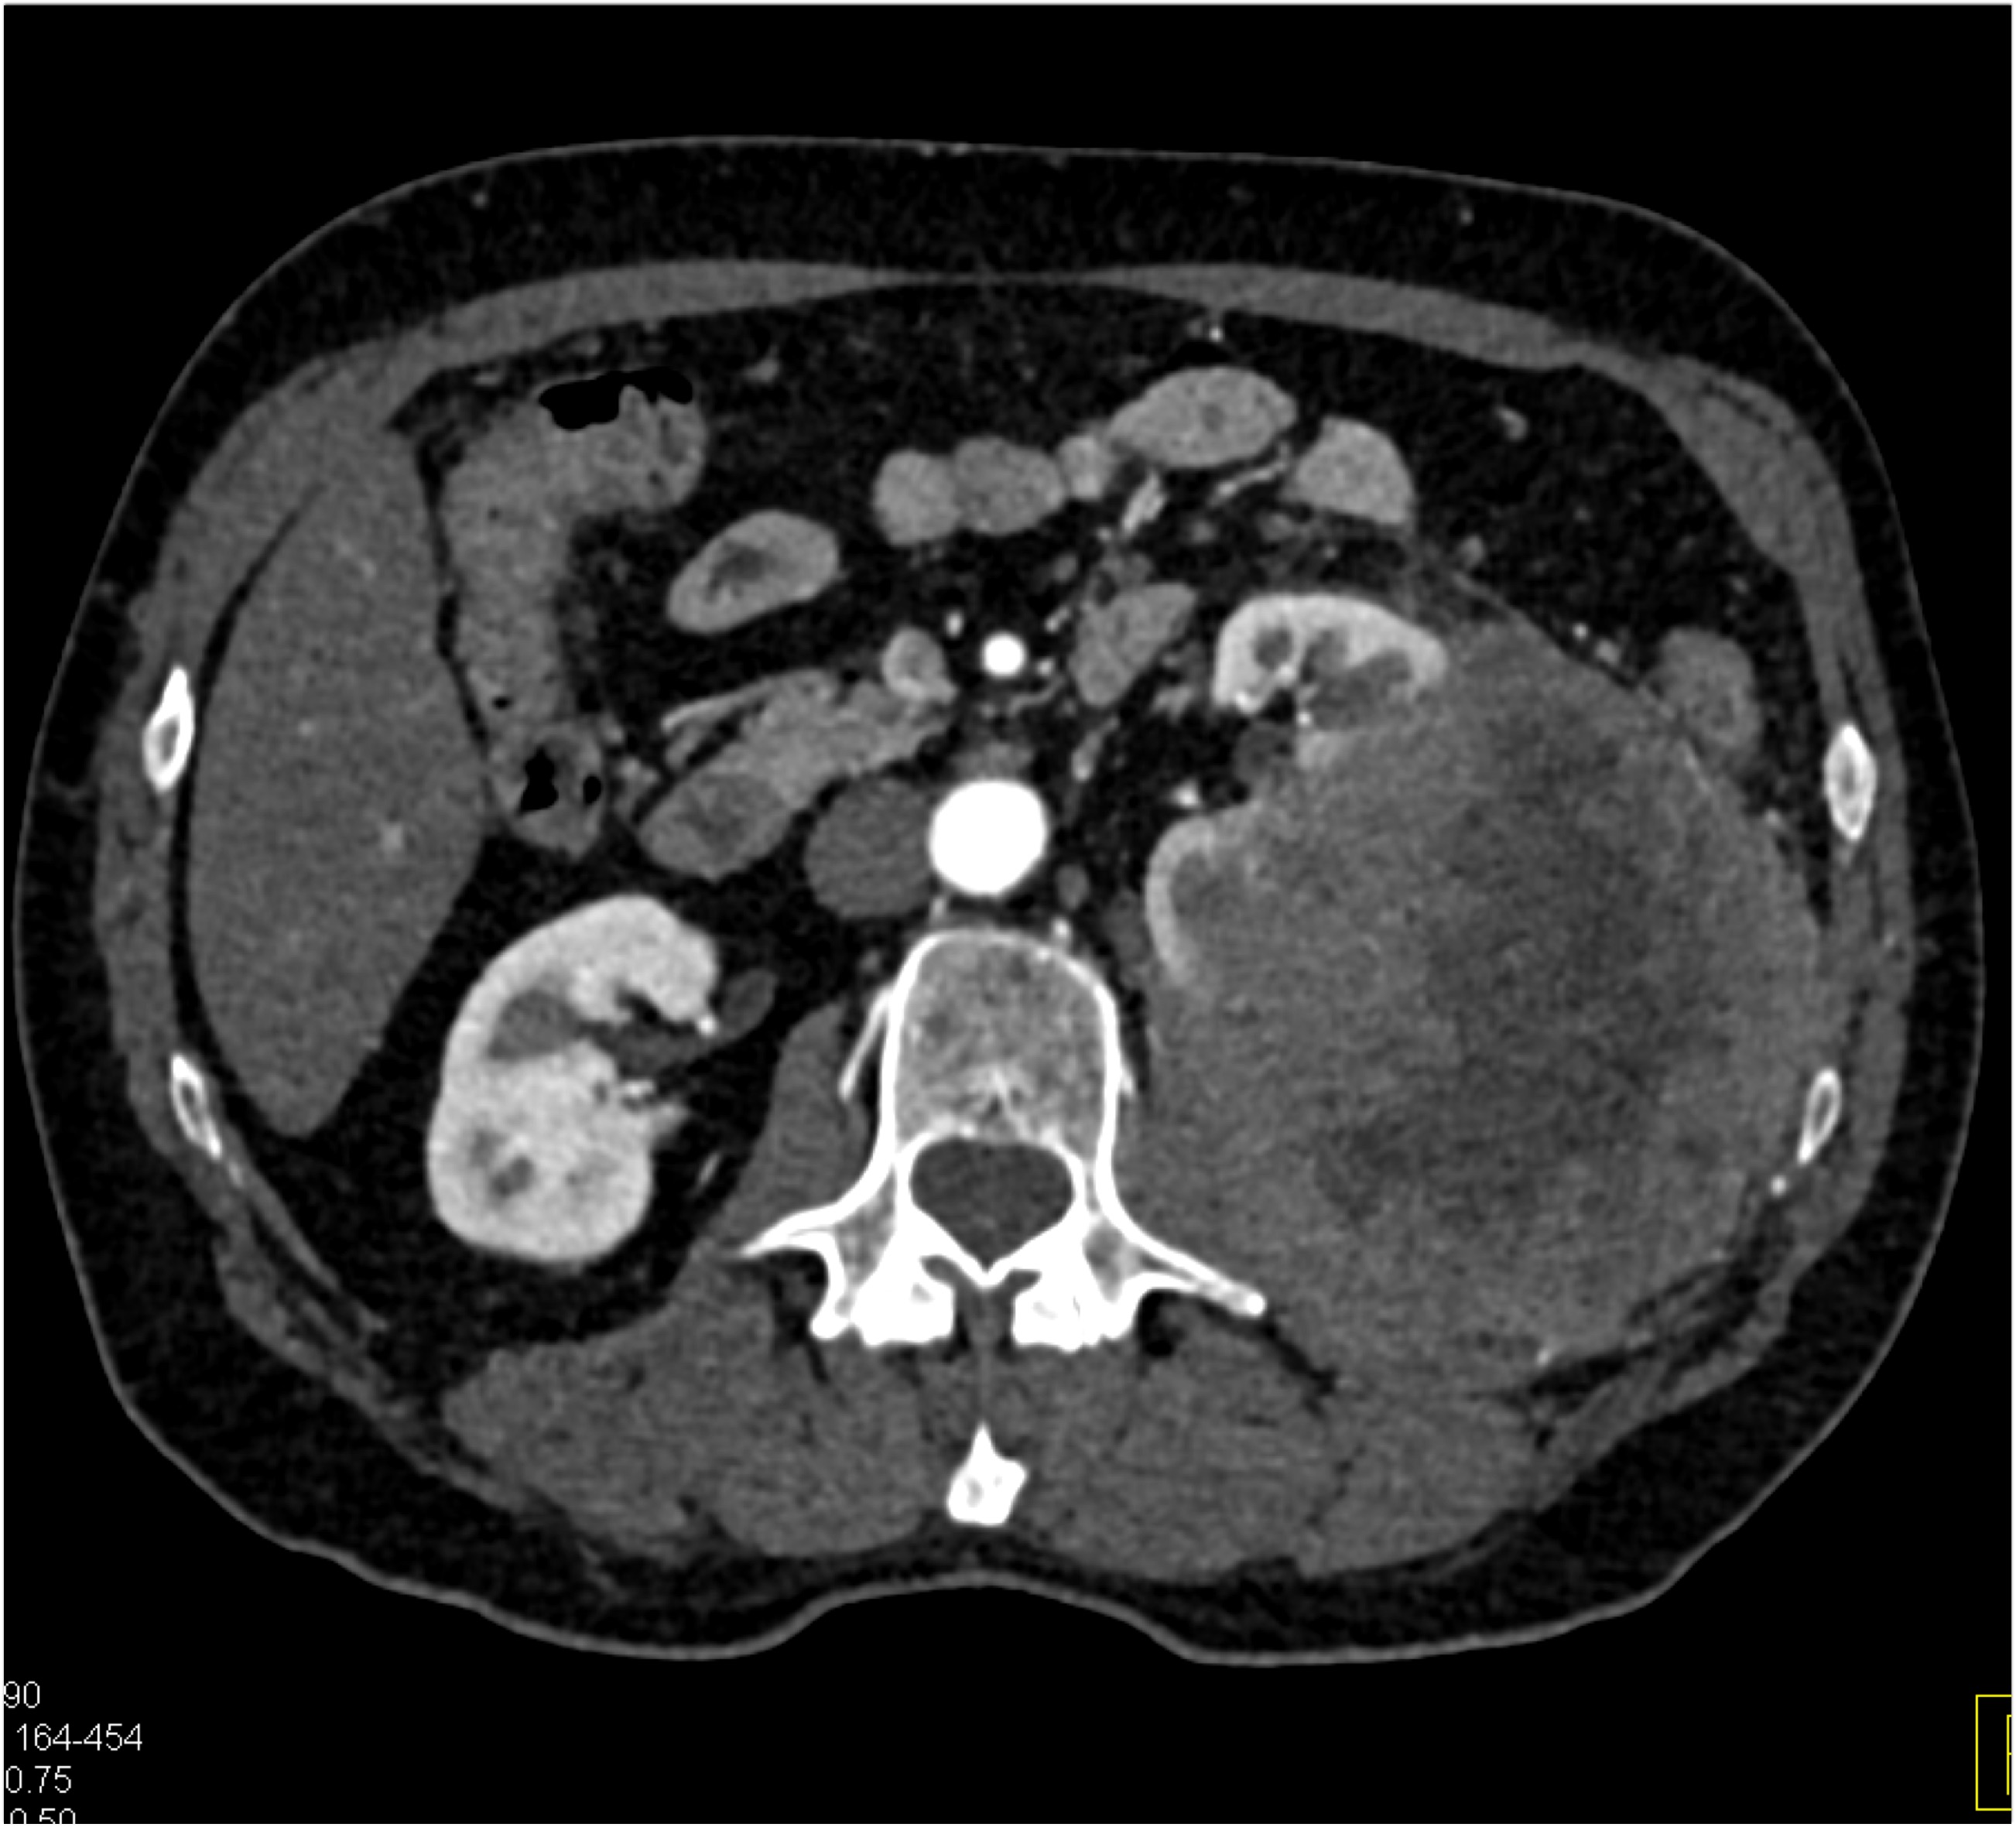

8) The most likely diagnosis in this case is?

clear cell renal cell carcinoma

large B-cell lymphoma

seminoma

renal abscess